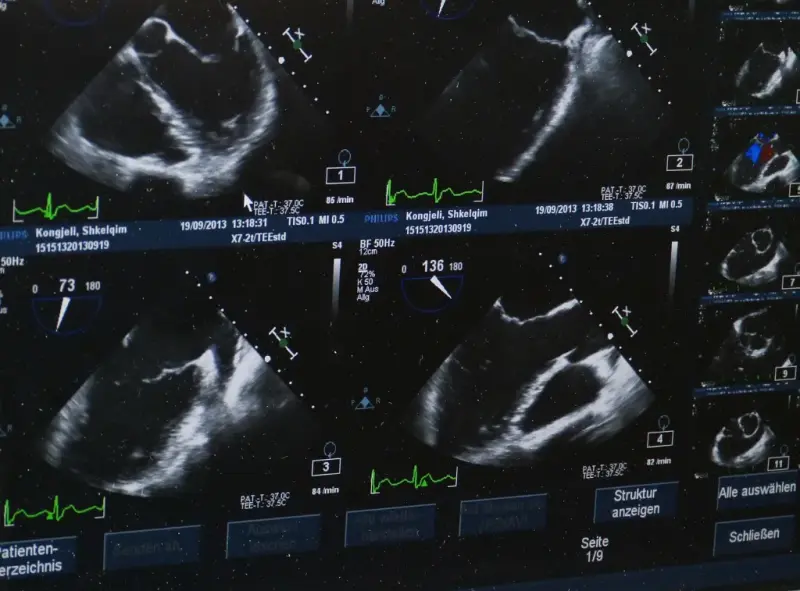

2. Kardiologia: echokardiografia, czyli USG serca, jest jednym z kluczowych badań w diagnostyce chorób serca. Umożliwia ocenę struktury i funkcji serca, pozwala wykryć nieprawidłowości w budowie zastawek czy naczyń krwionośnych.